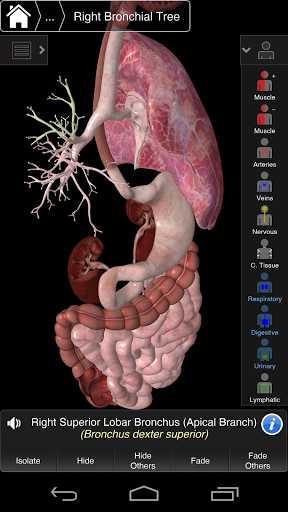

Essential Anatomy 3 representa lo último en tecnología 3D innovadora y diseño innovador. Un motor de gráficos 3D de vanguardia, creado a medida por 3D4Medical desde cero, alimenta un modelo anatómico altamente detallado y ofrece gráficos de calidad excepcional que ningún otro competidor puede lograr.

La aplicación representa un enfoque único para el aprendizaje de la anatomía general. Los gráficos no tienen paralelo y hacen que el aprendizaje, a través del uso de contenido informativo y características innovadoras, sea una experiencia rica e interesante.

Esta aplicación incluye anatomía esencial para 10 sistemas:

⁃Respiratorio

NUEVA TECNOLOGÍA 3D

Essential Anatomy 3 es receptivo, visualmente impactante y sin esfuerzo. La aplicación es totalmente en 3D, lo que significa que puedes ver cualquier estructura anatómica de forma aislada y desde cualquier ángulo.

---- Más de 4,000 estructuras anatómicas altamente detalladas

---- Nomenclatura latina para cada estructura anatómica